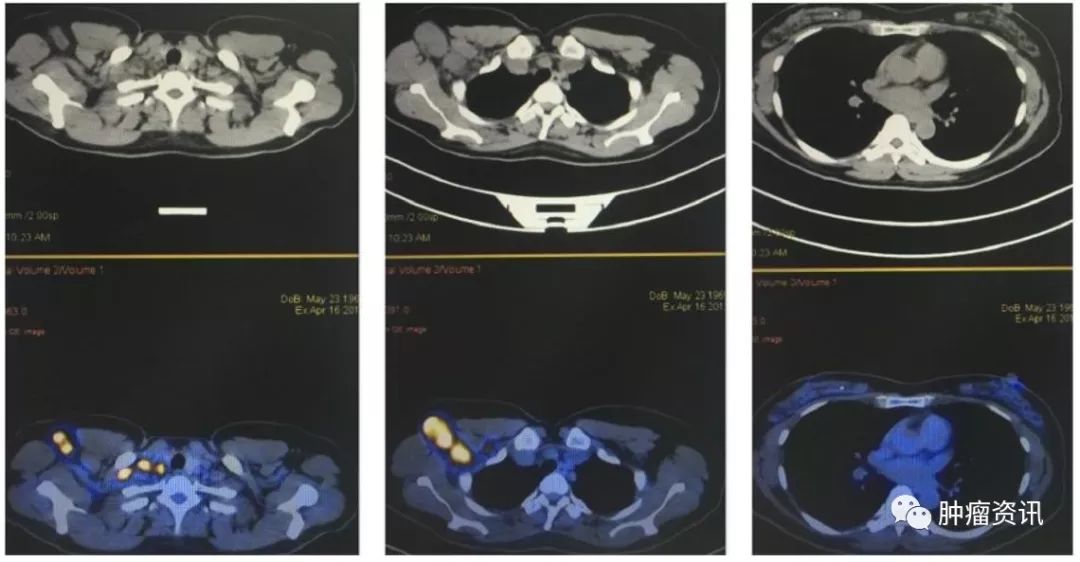

实验室检查:血肿瘤标记物:CA153 32.4U/ml,CA125 46.43 U/ml,CEA 5.92 ng/ml。乳腺MRI示(图1):右腋窝、右锁骨上肿大淋巴结,最大为38mm×38mm,强化明显,符合转移。右胸廓内动脉旁小淋巴结,9mm×8mm,强化明显,不除外转移。双乳可见直径为3~6mm多发小结节,等T1稍高T2信号,考虑为增生结节,余未见明显。颅脑MRI未见明显异常。PET-CT示(图2):右锁骨上、右腋窝多个肿大淋巴结,最大约为25mm×32mm,SUVmax为18,符合转移瘤,余未见明显异常。

图2 患者入院PET-CT